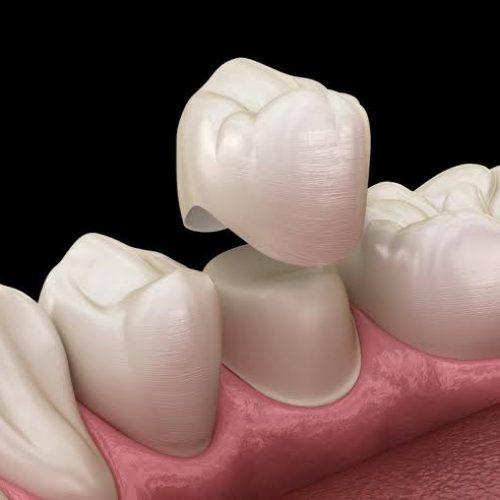

•روکش دندان (برای محافظت و زیبایی)